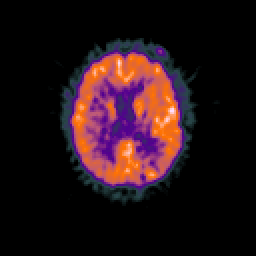

Glioma overlay -- Slice #70

[Home][Help][Clinical] Slice 70